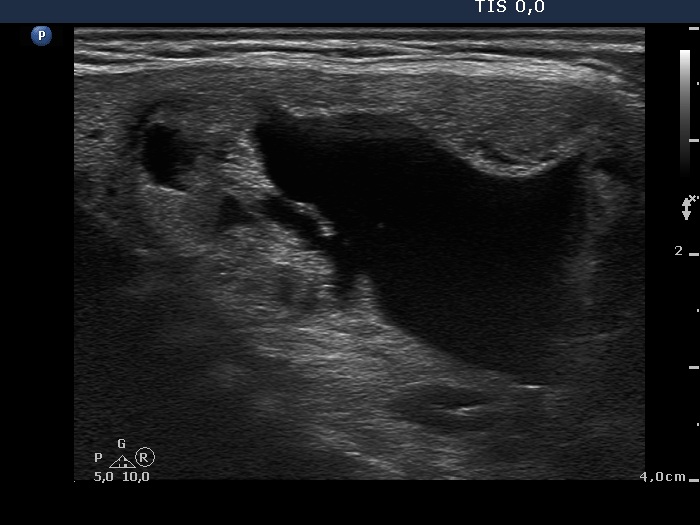

Intranodular hyperechogenic figures - case 608 (ultrasonographic picture 5)

Isthmus, longitudinal view. There are several smaller cystic areas within the lesion. On this image, the lesion seems to be a central-type cyst.